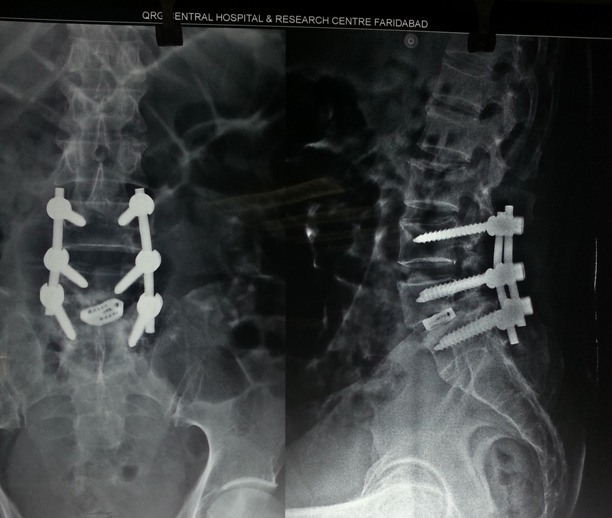

LUMBAR SPINE SURGERY

lumbar

TLIF Cage Placement and Fixation.

Dorsolumbar spine Fixation.

Lumbar decompression and fixation.